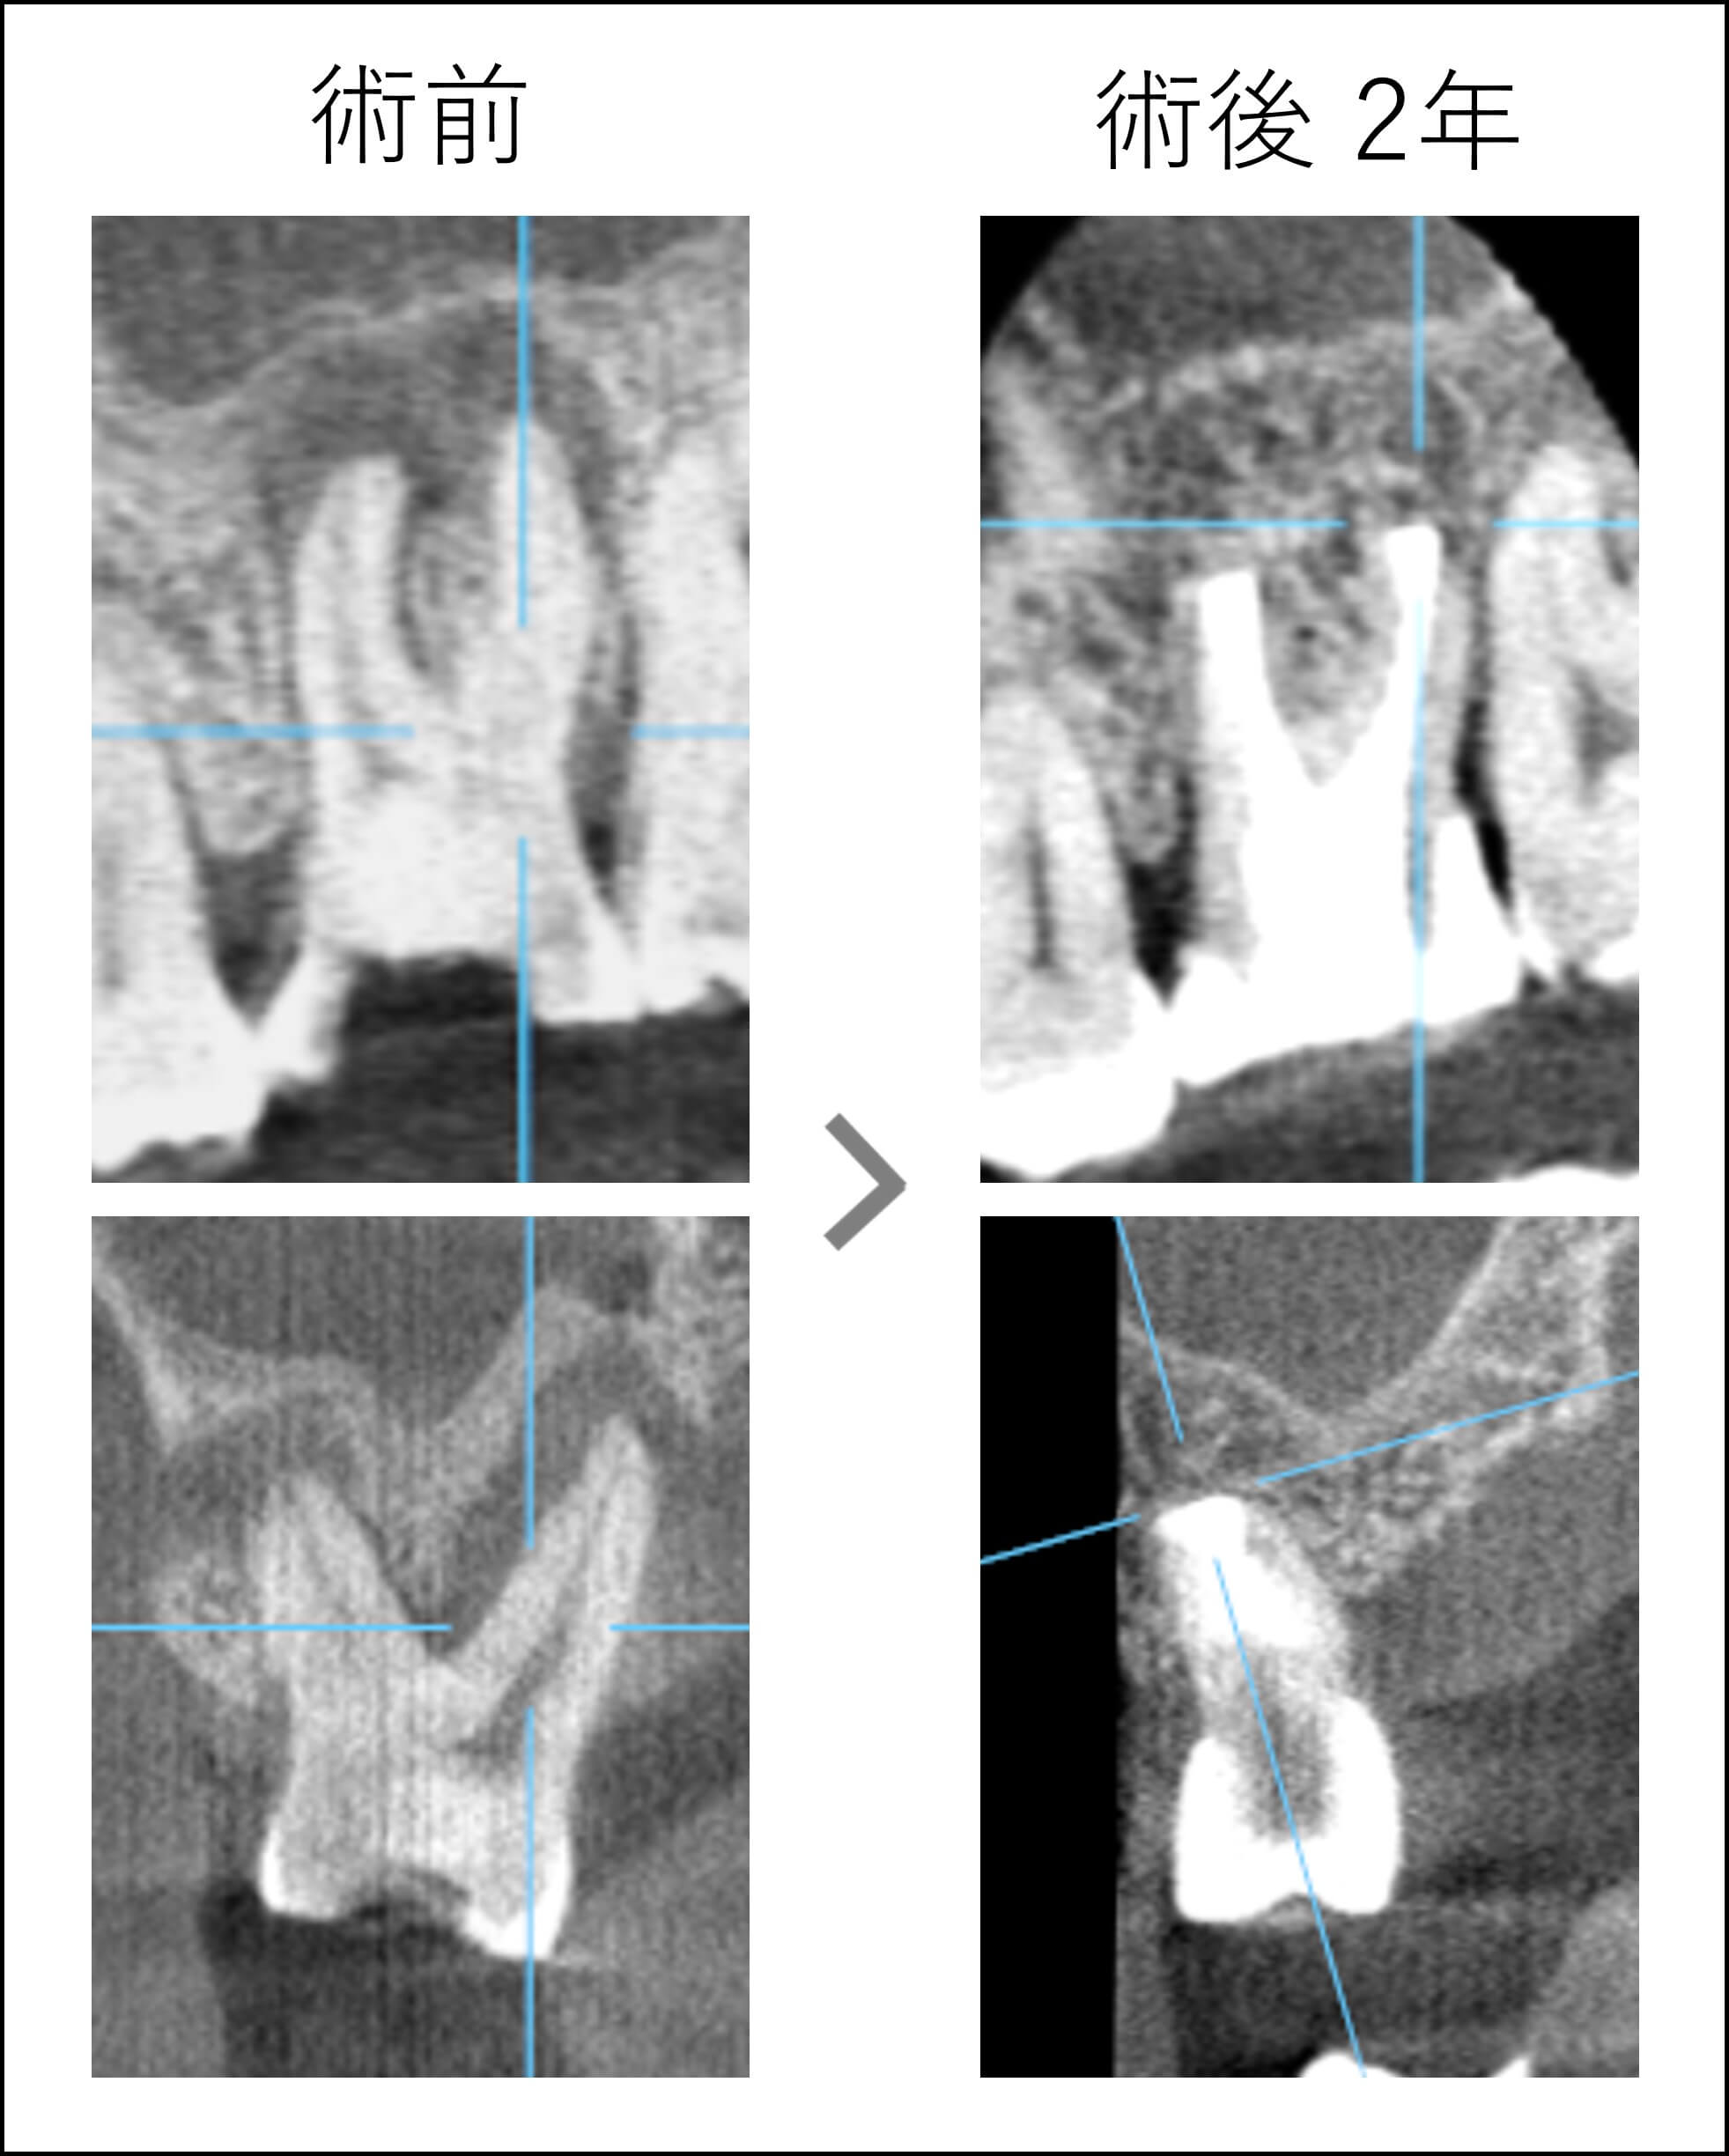

現在術後2年ですが、経過良好です。症状はすべて消えました。ここまでくれば、破折するまで持つと思いますので、今後はより一層の咬合チェックが必要になります。

CBCTは治療の結果を患者様にもしっかり伝えられる最適なツールだと思います。

比較することが大事で、治療前後どちらの資料が欠けてもこの説明はできません。